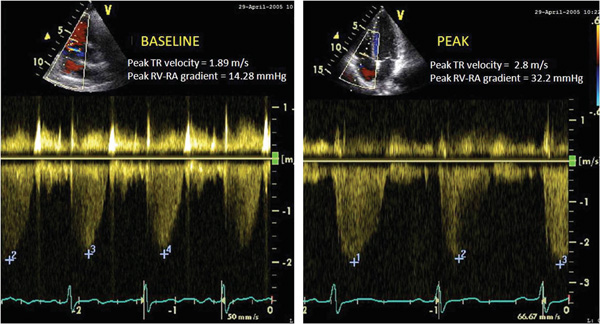

Fig. (1)

Peak tricuspid regurgitation jet velocity at rest (

A

) and at peak exercise (

B

).